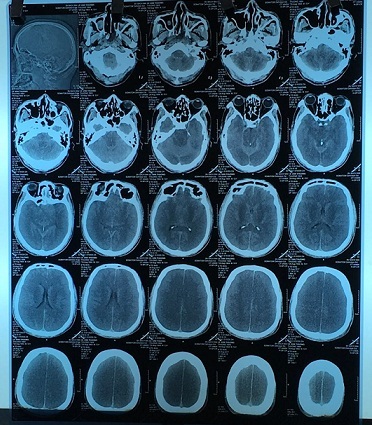

Khi mổ để đặt ống truyền dưỡng chất, bác sĩ phát hiện toàn bộ dạ dày của bệnh nhi đã teo nhỏ, xơ cứng. Thực quản và ruột nối với dạ dày bị bịt kín khiến thức ăn không thể lọt qua.

Sau đó, bệnh nhân sau đó được tạo hình dạ dày từ ruột non và dần dần tự uống được sữa, ăn được cháo loãng, thể trạng ngày một tốt hơn.